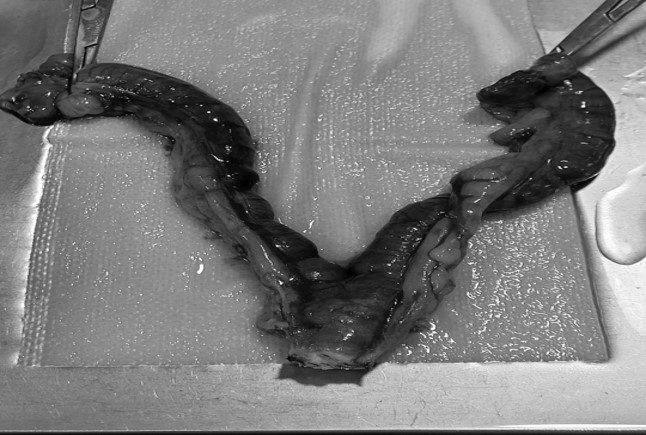

제거한 자궁과 난소

자궁체 절제 → 제거한 자궁 → 자궁내 혈액성 농성 삼출물

강아지의 자궁축농증이 있는 자궁은 이렇게 쌓인 고름처럼 사진처럼 팽창하게 된다.

이 환자의 자궁 내에는 혈액성 농성 삼출물로 가득 차 있었습니다.